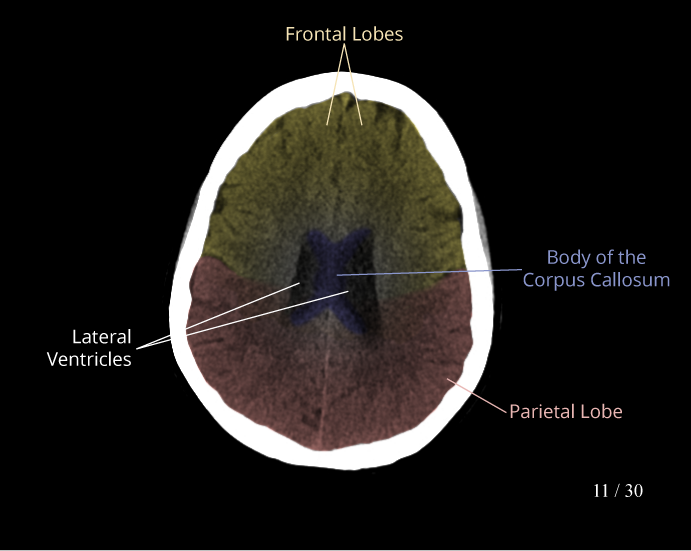

CT Brain Anatomy